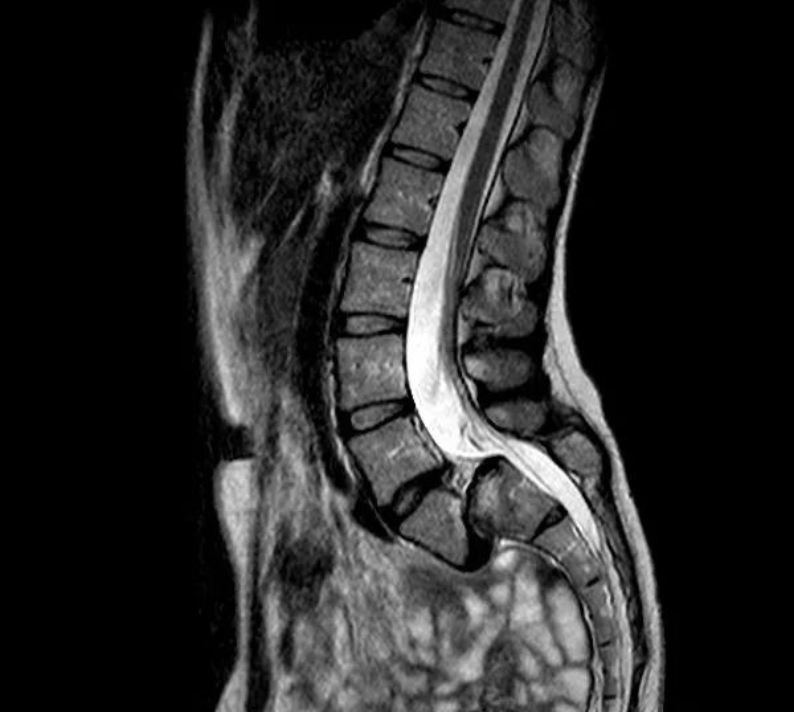

腰4椎体向前IV度滑脱

V形